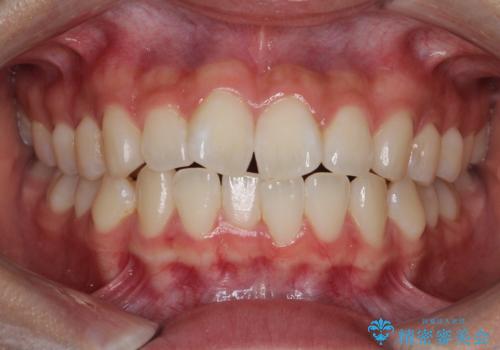

![[ インビザライン矯正 ] マウスピース矯正で治す、前歯のガタつきの症例 治療後](https://seimitsushinbi.jp/wp/wp-content/uploads/2022/02/IMG_1698-500x350.jpg?v=1644473356)